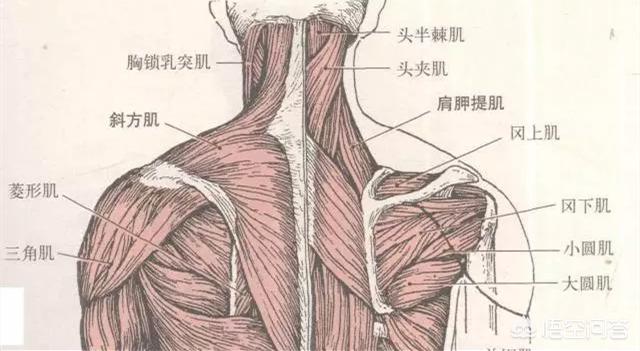

Comme indiqué ci-dessus, ce muscle est anatomiquement ce que l'on appelle un "levator scapulae (anatomie)". Il se développe d'une part sur l'apophyse transverse des vertèbres cervicales 1 à 4, et d'autre part à l'endroit même où se trouve le point douloureux (l'angle supérieur interne de l'omoplate). Sa fonction principale est la suivante :Lorsque la fin du point de douleur est fixéeLa tête et le cou sont inclinés vers l'arrière lorsque les deux côtés sont contractés et raccourcis.Lorsque la tête est baissée pendant une longue période, elle s'étire progressivement lorsque la tête est tirée vers l'avant, jusqu'à ce qu'à la limite, lorsqu'il n'est plus possible de l'étirer davantage, il y ait une douleur à l'angle supérieur interne de l'omoplate, à l'extrémité stationnaire.。

2) Deuxième raison : bien que rares, lesFacilement mal diagnostiquéC'est le problème des releveurs de l'omoplate décrit plus haut. Une autre structure importante est le muscle oblique postérieur, comme indiqué ci-dessous :

La première raison est quePiégeage du nerf scapulaire dorsalRésultat. Le nerf scapulaire dorsal innerve principalement les muscles scapulaire et rhomboïde juste après la naissance.La région du bord médial de l'omoplate est située à l'endroit où s'attache le muscle rhomboïde, comme le montre l'illustration ci-dessous :

Un tel physique affectera directement le fascia rhomboïde attaché à l'omoplate dans le dos, vous voyez où les rhomboïdes se développent ?

Comme indiqué ci-dessus, le muscle rhomboïde est composé de deux parties, le petit muscle rhomboïde en haut et le grand muscle rhomboïde en bas, qui partent tous deux de l'apophyse épineuse sur la ligne médiane de la colonne vertébrale jusqu'au bord médial de l'omoplate. C'est par l'aspect du physique décrit ci-dessus que leLes rhomboïdes sont ensuite étirés sur les côtés, comme si l'on tirait sur un sac en plastique, et à un certain moment, une douleur apparaît dans la zone du bord médial de l'omoplate.L'arrière des épaules et l'arrière du corps ressentent comme un poids lourd. En même temps, vous aurez une sensation d'enfoncement et de lourdeur à l'arrière des épaules, comme si vous portiez une lourde charge sur votre dos ; et bien sûr, les rhomboïdes sont souvent faibles parce qu'ils ont été étirés pendant longtemps.Une omoplate à aile externe dont le bord médial fait saillie vers l'extérieur.Les femmes prédominent.

Beaucoup de mes amis pensent queUn cou est un cou, une épaule est une épaule, un dos est un dosque les trois n'ont pas grand-chose à voir l'un avec l'autre, en fait, cette idée est biaisée, de la part des étudiants en médecine, nous devrions prendre l'exemple de l'école de médecine.颈, épaule, dosRegardez-le comme un seul, à partir d'un seul muscle, et donnez une brève analyse de ce muscle, qui est lele muscle trapèze (du haut du dos et du cou)。

Si vous regardez de près, vous verrezCe trapèze.inclureBase du crâne, cou, épaules et dosLes muscles trapèzes des deux côtés sont étroitement liés et forment ensemble une structure rhomboïde, qui est essentielle au maintien de l'équilibre de la colonne vertébrale.Stabilisation du dosIl joue un rôle très important dans l'accomplissement de multiples activités au niveau du cou, des épaules et du dos.Le muscle trapèze est divisé en faisceaux supérieur, moyen et inférieur, et les différentes parties de la contraction permettent d'effectuer des mouvements différents。

En ce qui concerne les causes de la douleur, il convient tout d'abord de bien réfléchir si vous avez récemment effectué un travail qui sollicite les muscles. D'une manière générale, étant donné que la région de l'omoplate comporte de nombreux muscles (comme indiqué ci-dessous), les métiers particuliers tels que ceux qui lèvent souvent les bras peuvent provoquer des douleurs à l'arrière de l'omoplate en cas d'accumulation prolongée de la douleur. Cela peut être dû à la sollicitation des groupes musculaires à l'origine de la douleur. Si c'est pour cette raison, il peut être recommandé de se reposer, de se coucher à plat sur le lit, de prendre un sac d'eau chaude pour une compresse chaude (le sac d'eau chaude peut être enveloppé d'une serviette, pour éviter les brûlures), 3 à 5 fois par jour, chaque fois que la compresse chaude dure 20 minutes. Si les symptômes ne peuvent toujours pas être soulagés, il est recommandé de consulter un médecin.